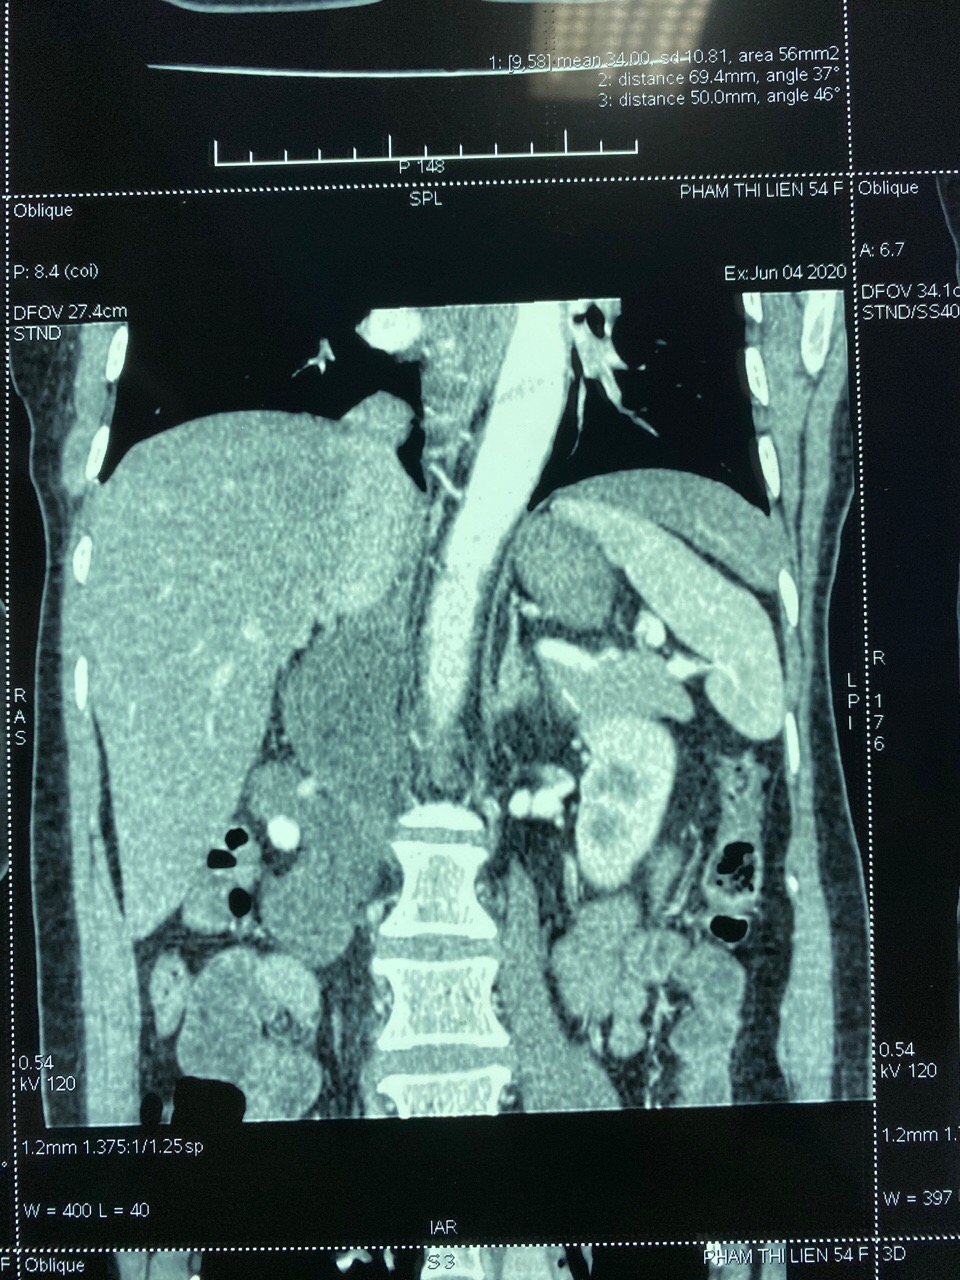

Ngay khi tiếp nhận bệnh nhân, các Bác sĩ của Bệnh viện Đa khoa tỉnh đã tiến hành thăm khám lâm sàng và cho bệnh nhân làm các xét nghiệm cơ bản và chuyên sâu. Kết quả xét nghiệm hormone ACTH, Cortisol, Catecholamin có kết quả bình thường. Hình ảnh chụp CT cho thấy phía sau phúc mạc phía bên phải cột sống, ngay cạnh và dưới tĩnh mạch chủ bụng, động mạch chủ bụng có vài khối giảm tỷ trọng kích thước 30x50x100 mm đè đẩy tuyến thượng thận phải, thận phải và tĩnh mạch chủ bụng, khối u này nằm sâu phía sau gan và trên thận. Bệnh nhân được chỉ định làm sinh thiết khối u bằng kim tru-cut dưới hướng dẫn của siêu âm, kết quả sinh thiết cho thấy đây là khối u sau phúc mạc thể Schwannoma.

Hình ảnh khối u trên phim chụp CT scanner